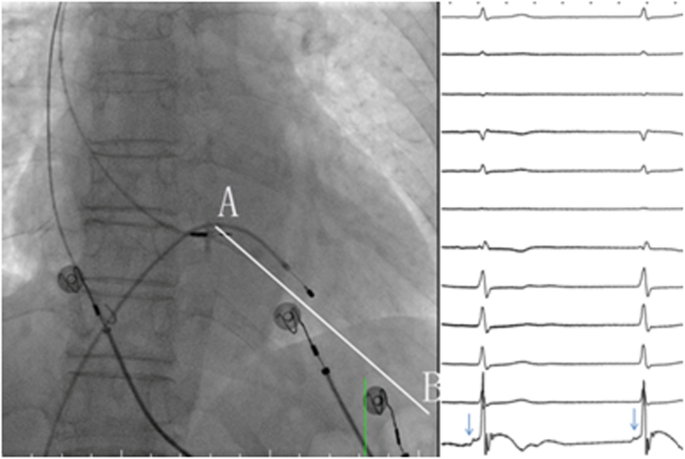

Pacing localization

Pace mapping at 3 V and 0.4 ms was performed to identify the ideal implantation site during unipolar tip pacing (UTP) with the following criteria. The paced QRS complex in lead V1 should display a “W” morphology with a mid-notch close to the bottom [16]. Bidirectional waves should be visible in one of the inferior wall leads (Fig. 4). The paced QRS duration at 10 V/0.4 ms should be less than at 3 V/0.4 ms.

The paced ECG at the ideal implantation site. Left plane: the paced ECG at the ideal implantation site. During unipolar tip pacing, the paced QRS complex in lead V1 displayed a “W” morphology. Bidirectional waves were visible in one of the inferior wall leads. Right plane: baseline ECG (B) and bipolar paced ECG (P) at LBB. The baseline ECG showed a complete RBBB morphology with a QRSd of 156 ms that was corrected by bipolar LBBAP to a narrow QRSd of 116 ms. LBBAP, left bundle branch area pacing